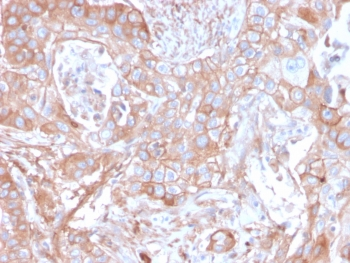

IHC staining of FFPE human pancreatic carcinoma with CD73 antibody (clone NT5E/2545). HIER: boil tissue sections in pH9 10mM Tris with 1mM EDTA for 10-20 min and allow to cool before testing.

IHC staining of FFPE human colon carcinoma with CD73 antibody (clone NT5E/2545). HIER: boil tissue sections in pH9 10mM Tris with 1mM EDTA for 10-20 min and allow to cool before testing.